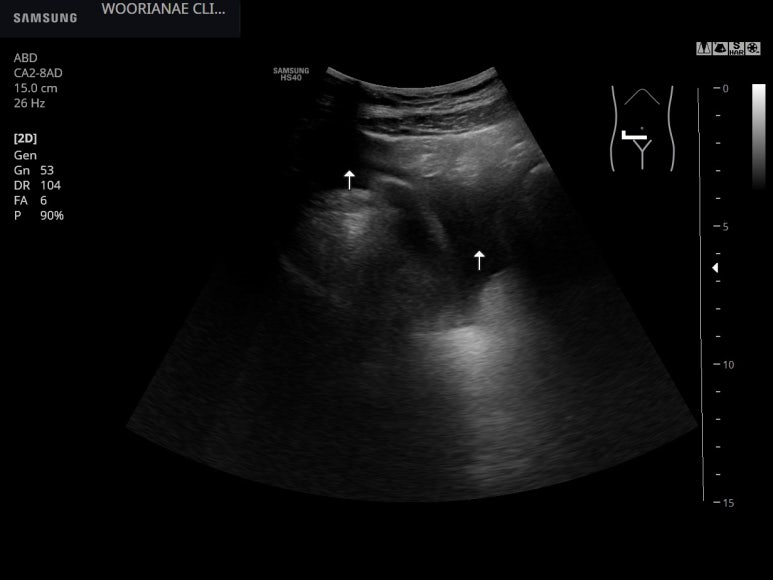

S1, 미상엽의 비대가 상당하게 느껴지며

담낭의 벽에 부종이 있다. 결론적으로 복수가 차는 현상과 같이 보았을때 혈액의 총단백/알부민 수치가 떨어져 있을 것이다. 3개월전과 달리

우엽과 S4 사이의 요철변화

우엽과 횡경막 사이에 복수가 발생하였다.

간문맥의 직경이 커져 있다.

표면의 요철변화

미상엽의 전후 직경이 작년에 5 cm 정도였었다. 지금은...